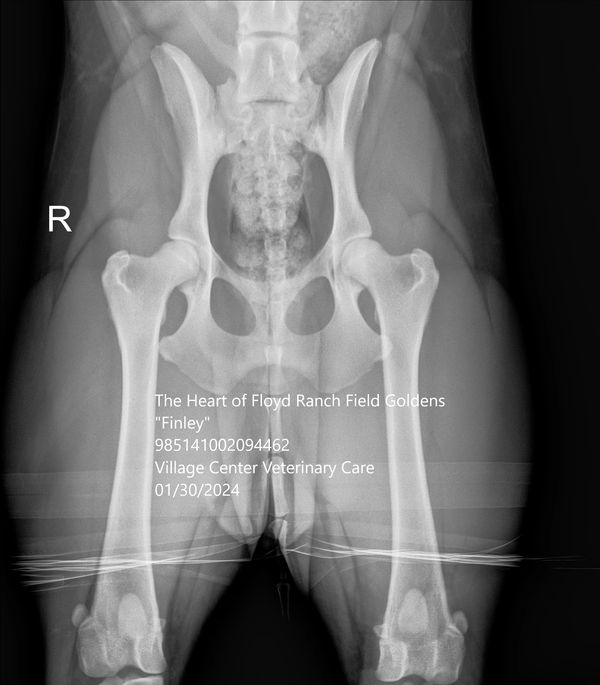

Finley has "Excellent" hips